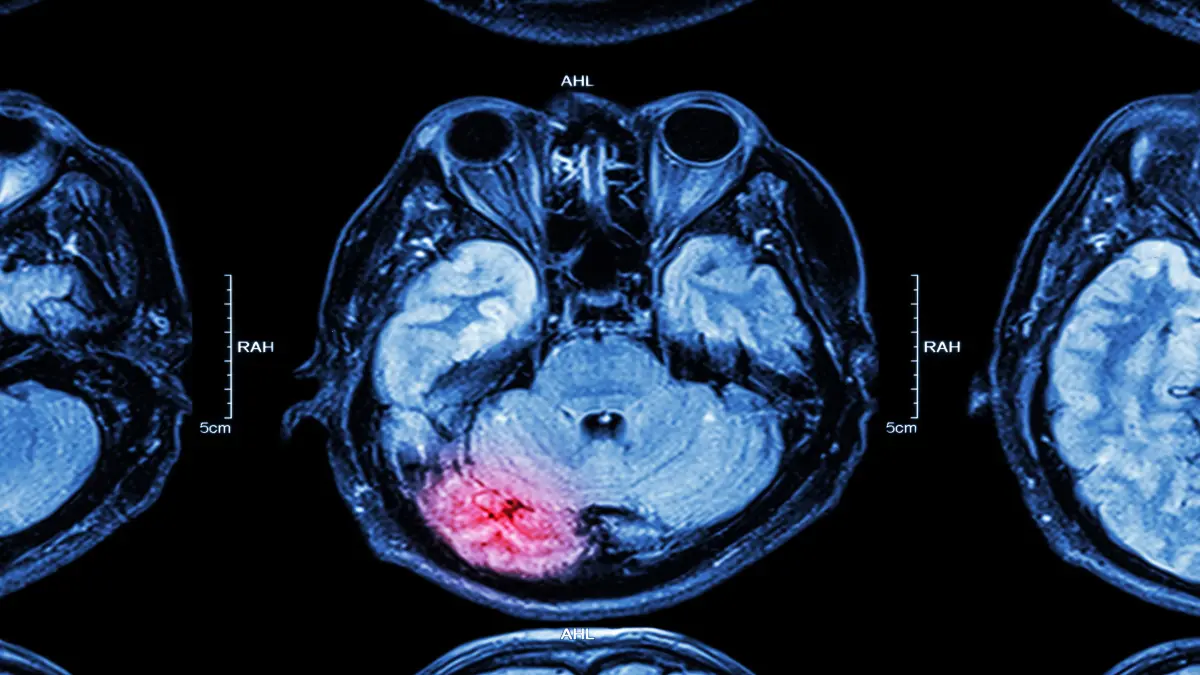

Epilepsie infolge von Hirntumoren behandeln